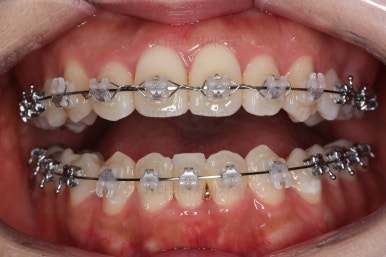

교합과 중앙선 및 디테일을 맞춰 나갑니다.

부산재교정 이니만큼 원하는 부분을 최대한 수용하여 개선하고 마무리를 합니다.

중앙선, 교합, 앞니 맞물림 등 모든 것이 좋아졌네요.